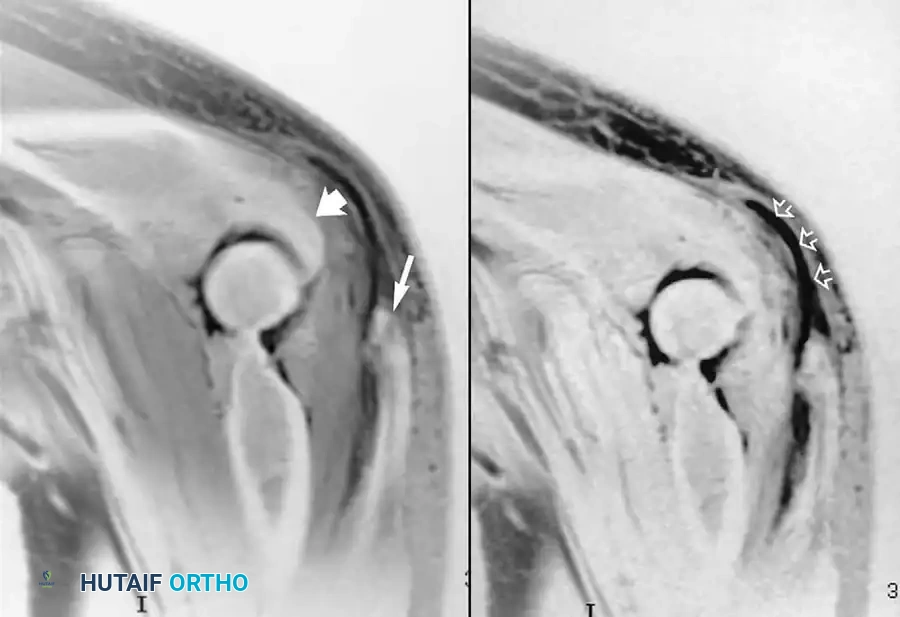

يلعب الرنين المغناطيسي، وخاصة الرنين المغناطيسي المفصلي (الذي يتضمن حقن صبغة داخل المفصل)، دوراً حاسماً في تقييم هذه الإصابة. فهو يكشف بدقة عن التمزقات الجزئية أو الكاملة في الرباط.

صورة رنين مغناطيسي مفصلي تظهر تمزق جزئي في الرباط الجانبي الزندي للكوع